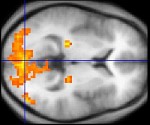

Poszukiwania biologicznych podstaw świadomości i pamięci to chyba najbardziej fascynujące zadania neurobiologii. O ile świadomość nadal wymyka się badaczom, to z pamięcią radzą oni sobie całkiem dobrze. Dotąd znaleziono jedynie siedlisko pamięci krótkotrwałej – okazała się nią struktura w mózgu zwana hipokampem.

Czy wiesz, dlaczego po uderzeniu w tył głowy widzisz gwiazdy? Odpowiedzialne są za to płaty potyliczne – zaangażowane przede wszystkim i prawie wyłącznie w procesach związanych ze wzrokiem. Ale najważniejsze i najbardziej zaawansowane są płaty czołowe, kilkakrotnie większe proporcjonalnie do reszty mózgu człowieka niż u zwierząt. To część odpowiedzialna za podejmowanie decyzji, planowanie, hamowanie impulsów, wyciąganie wniosków itd., jak również za ruch i za mówienie. Płaty skroniowe są szczególnie ważne dla słuchu, w tym dla rozumienia mowy. Gdy mówisz: „coś mi to przypomina”, pracują z kolei płaty ciemieniowe, które odpowiadają, w przedniej części, za czucie ciała, np. dotyk, ciepło itp., a w tylnej i dolnej – za kojarzenie.